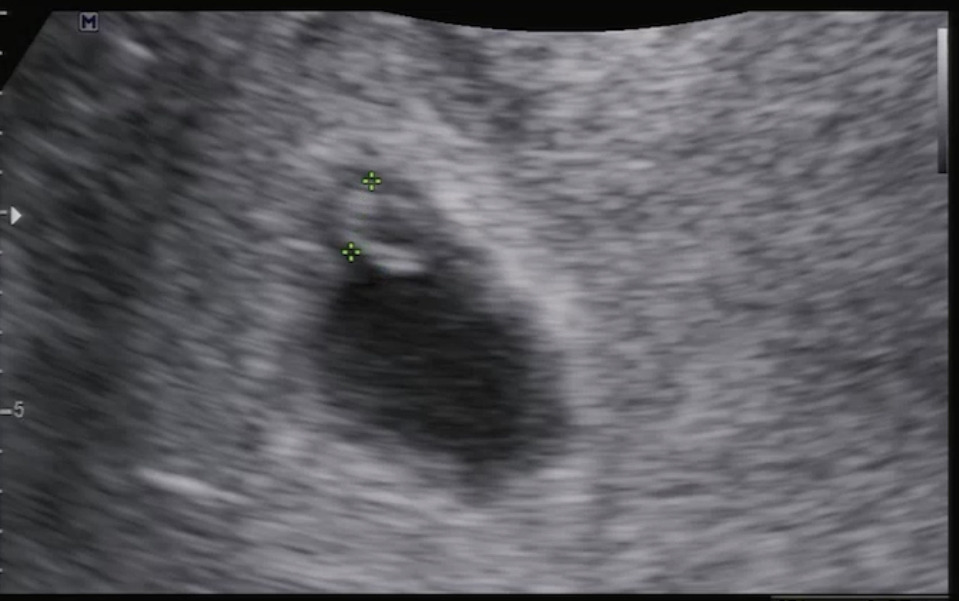

의사 선생님의 말처럼, 처음 만난 파이리는 아기집 구석에서 발견됐다. 가운데 넓은 공간을 두고 굳이 구석으로 파고드는 중이었다.

초음파 사진을 유심히 보던 아내가 재밌다는 듯 얘기했다. 파이리가 구석으로 파고드는 게 딱 내가 잘 때 모습이라며 웃었다.